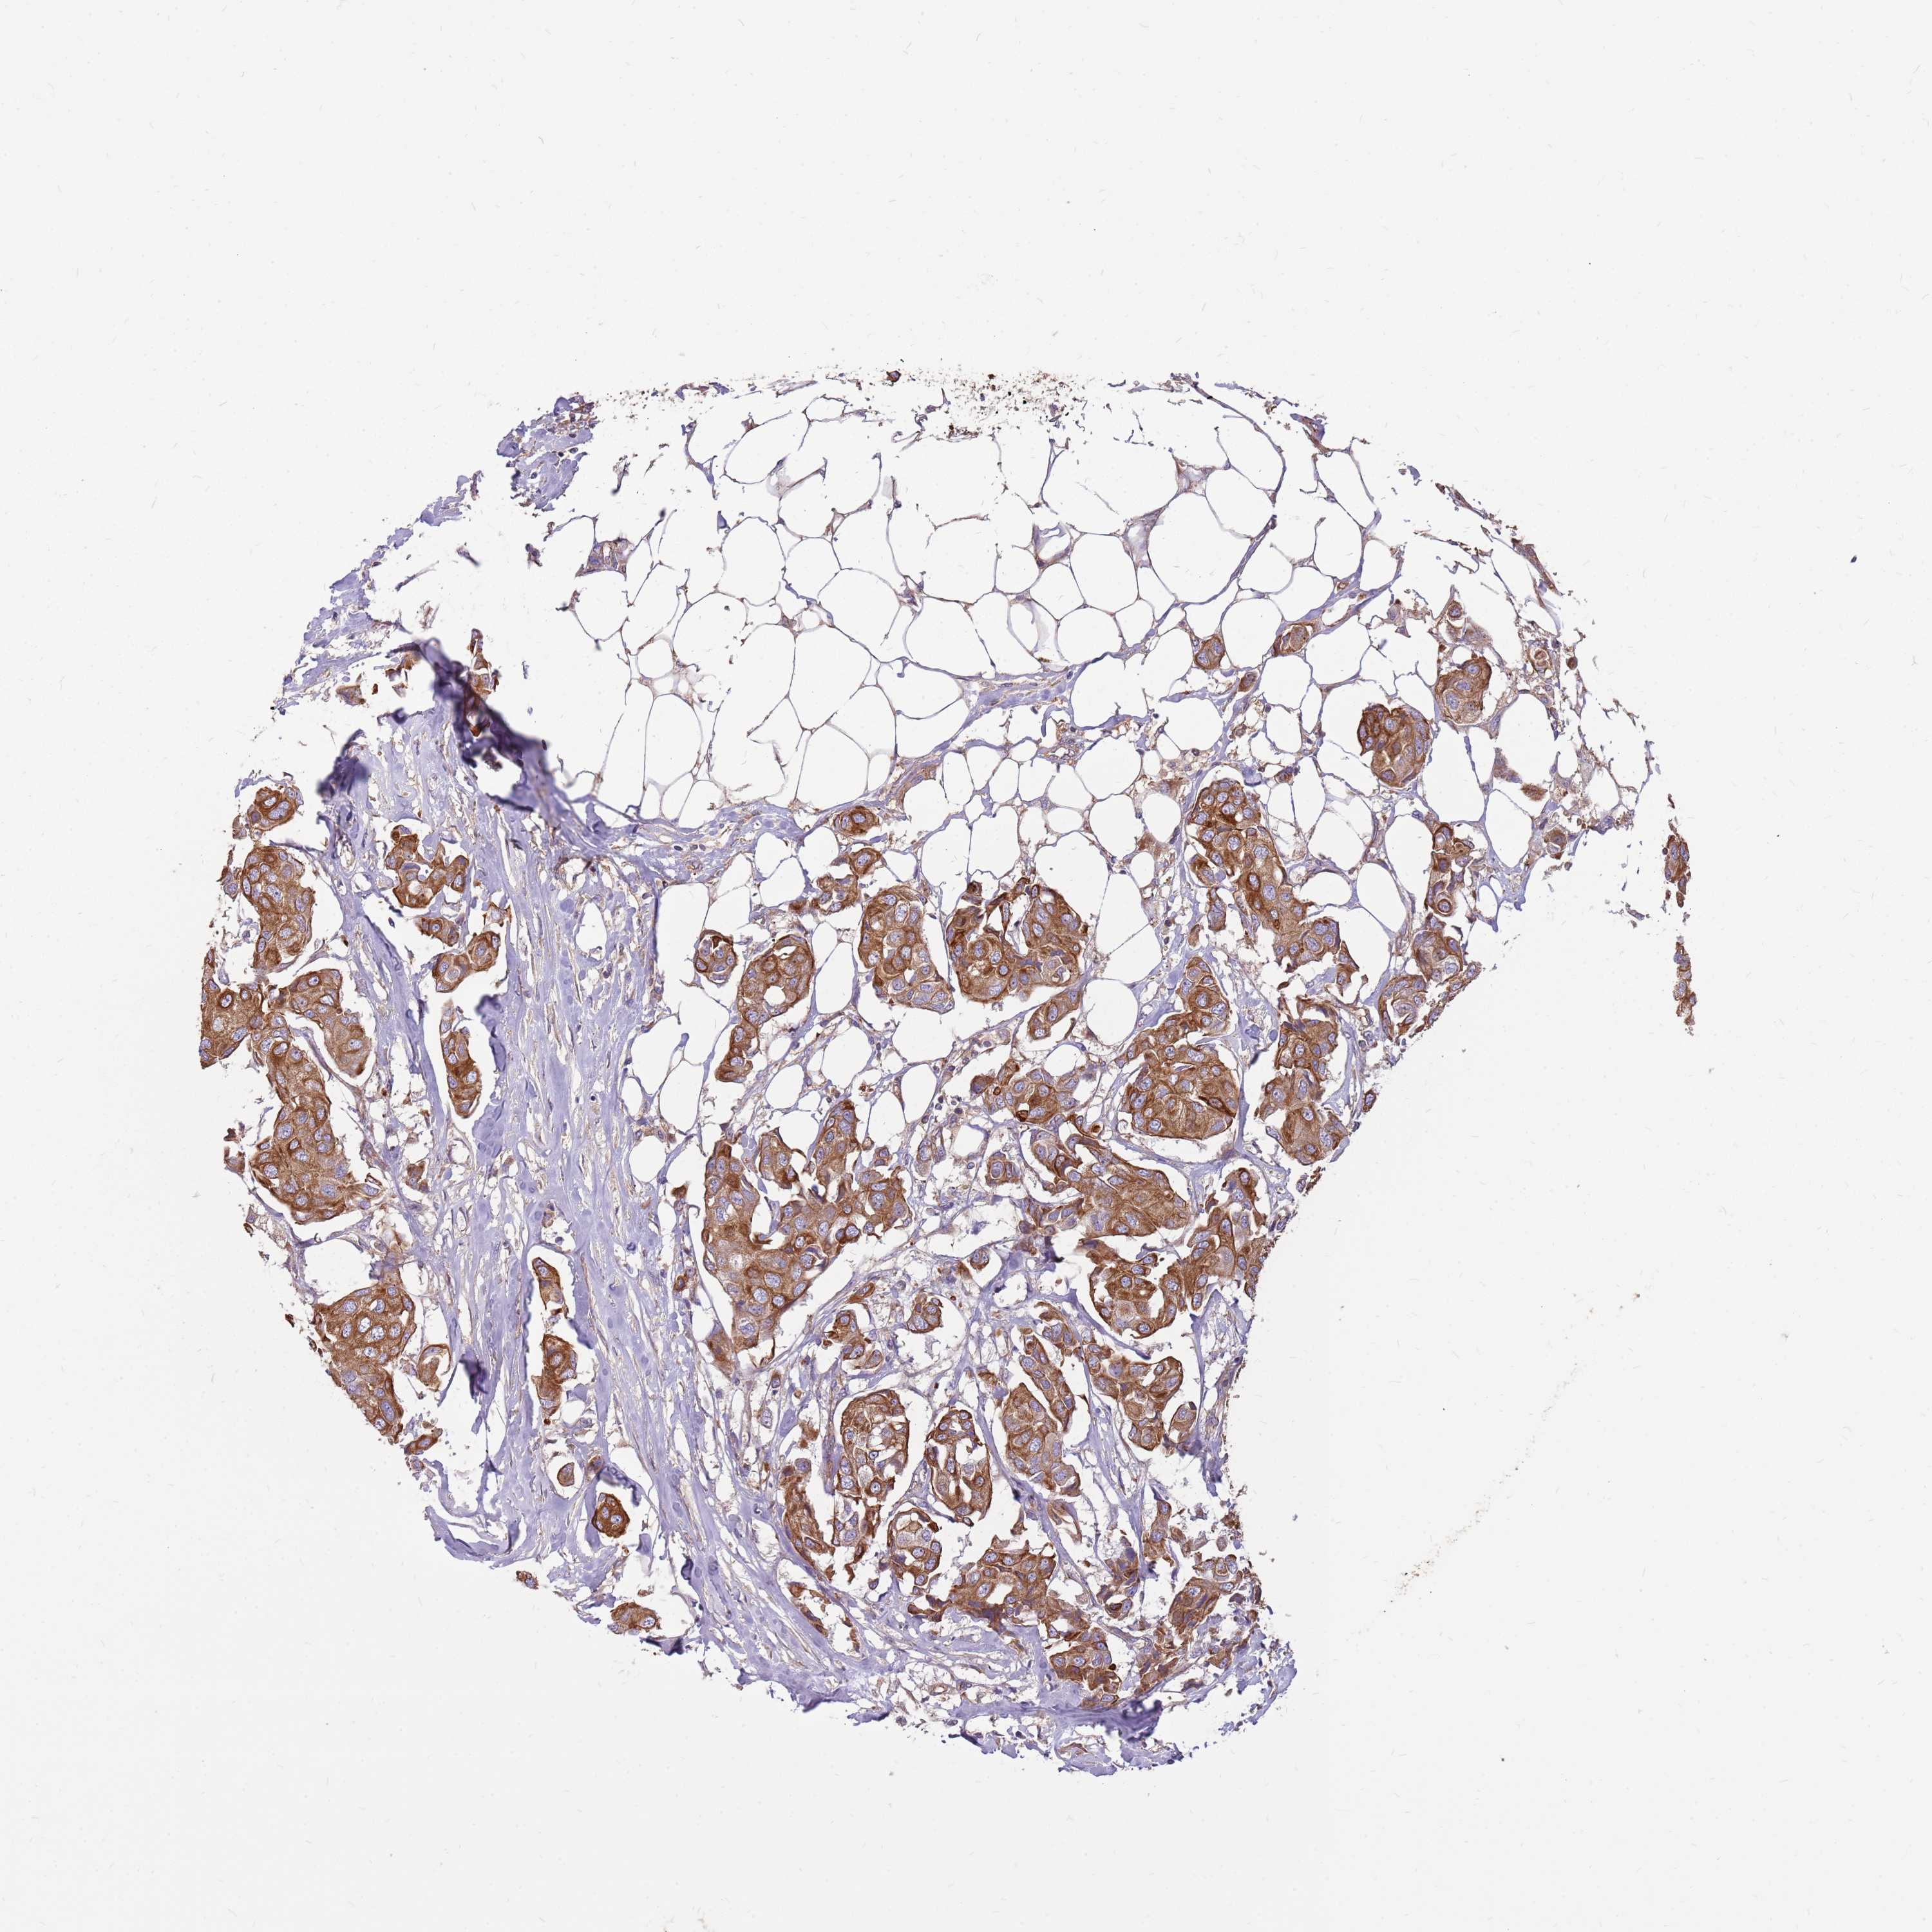

CANCER BREAST CANCER Show tissue menu

BRCA TCGA BRCA VALIDATION PROTEIN EXPRESSION